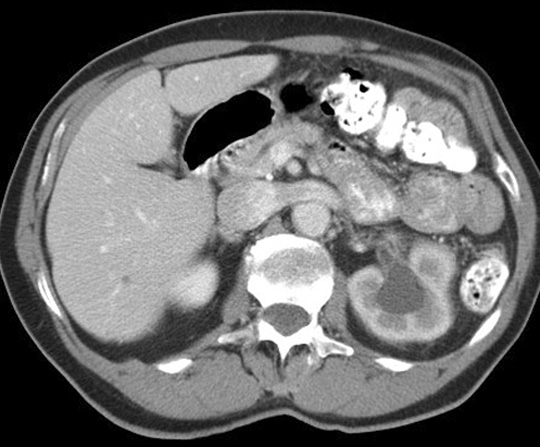

Note the relationship of the duodenal bulb. Click the image for labeling.